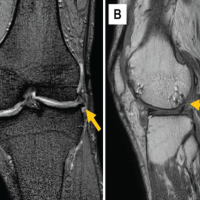

A 2-year-old male, with no prior medical history, presented to the emergency department due to a complaint of 3 days of torticollis. Per the parents, no trauma had occurred previously nor the patient had any recent upper respiratory infections. Upon physical examination, the patient was noted to have painful torticollis with the neck rotated and flexed laterally in a fixed position. The rest of the physical examination was without abnormalities. A radiograph of the neck was then requested where no anomalies were found (Fig. 1). The patient was then discharged home with symptomatic treatment. The patient returned 3 days later due to the persistence of the same symptoms. A magnetic resonance imaging was then obtained, which demonstrated a subtle abnormality of the posterior arch of C2, with no signs of acute trauma (Fig. 2).